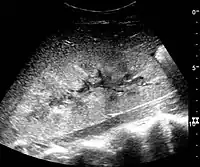

The kidney is divided into parenchyma and renal sinus. The renal sinus is hyperechoic and is composed of calyces, the renal pelvis, fat and the major intrarenal vessels. In the normal kidney, the urinary collecting system in the renal sinus is not visible, but it creates a heteroechoic appearance with the interposed fat and vessels. The parenchyma is more hypoechoic and homogenous and is divided into the outermost cortex and the innermost and slightly less echogenic medullary pyramids. Between the pyramids are the cortical infoldings, called columns of Bertin (Figure 1). In the pediatric patient, it is easier to differentiate the hypoechoic medullar pyramids from the more echogenic peripheral zone of the cortex in the parenchyma rim, as well as the columns of Bertin (Figure 2).[1]

Figure 1. Normal adult kidney. Measurement of kidney length on the US image is illustrated by ‘+’ and a dashed line. *Column of Bertin; ** pyramid; *** cortex; **** sinus.[1]